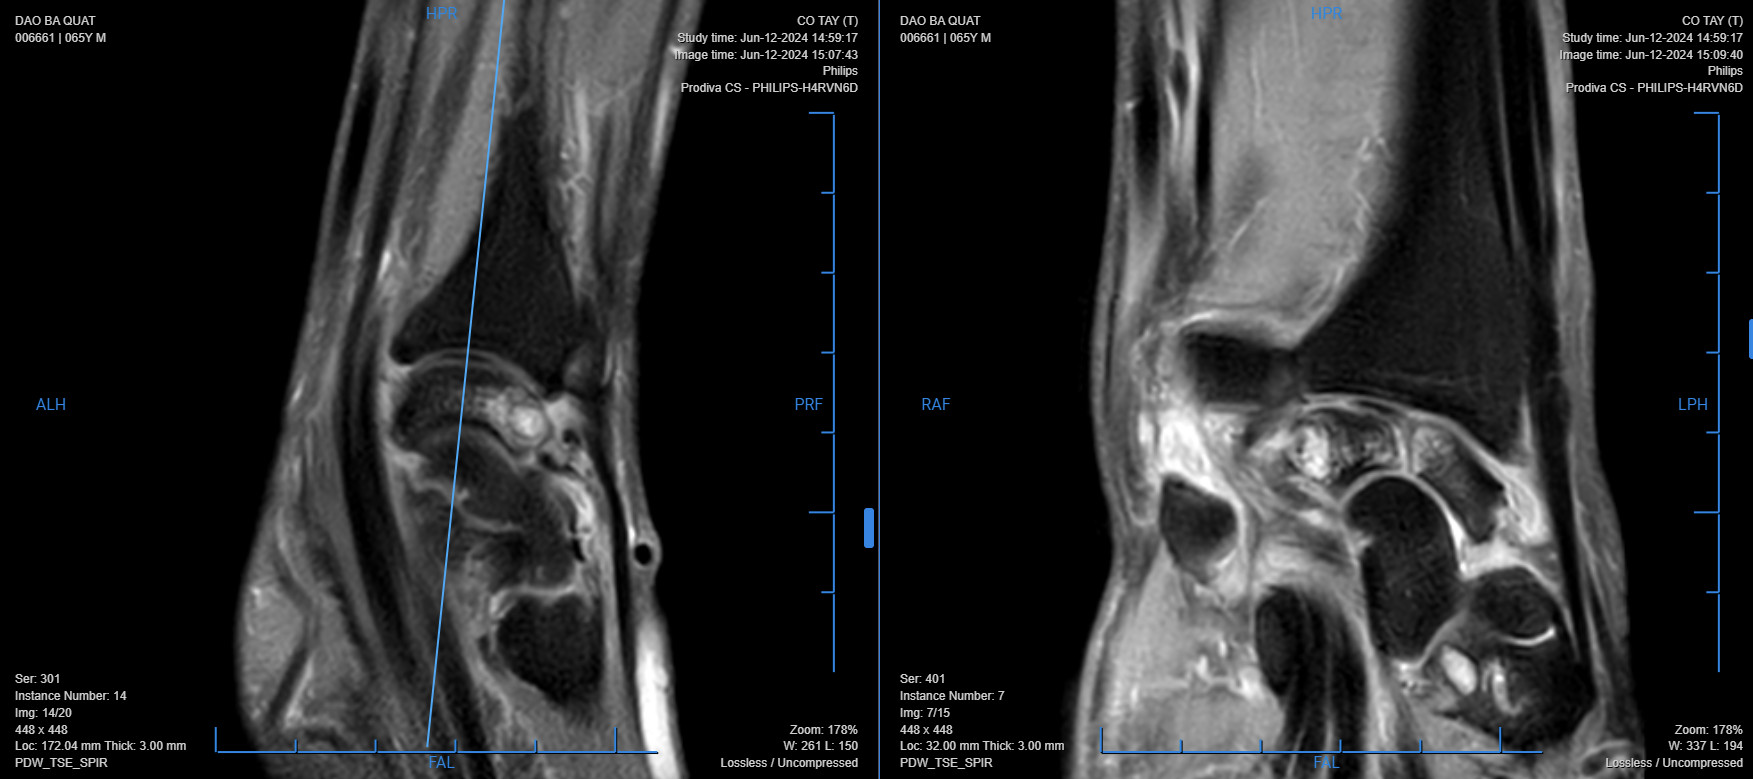

Bệnh nhân bị sưng đau khớp cổ tay 2 bên, ấn đau các xương bàn tay, vận động khó khăn, đã đi thăm khám nhiều nơi nhưng không đỡ. Kết quả chụp X Quang 2 tay cho thấy tiêu khuyết xương không đều xương thuyền, xương xương nguyệt khớp cổ tay và kết quả chụp cộng hưởng từ cho thấy tiêu xương mất cấu trúc xương, phù nề tủy xương thân các xương thuyền, xương nguyệt, xương thê, xương móc đầu gần xương bàn 2 bên (T). Đồng thời phát hiện bệnh nhân có bệnh lý nền bị gout. Qua quá trình thăm khám và kết quả cận lâm sàng, bác sĩ chẩn đoán bệnh nhân bị Kienbock trên nền bệnh gout và chỉ định thực hiện phẫu thuật kết hợp xương trên màn hình tăng sáng.